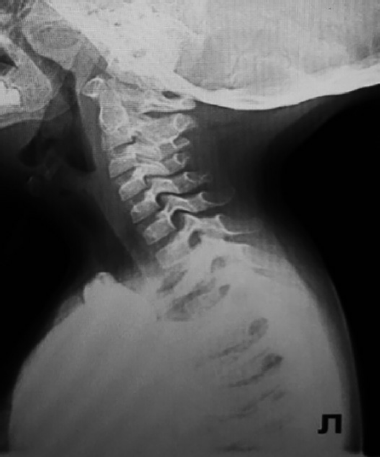

При назофаринголарингоскопии выявлены признаки ларингомаляции 2-го типа: надгортанник свернут в виде желоба, черпалонадгортанные складки укорочены, увеличенные черпаловидные и клиновидные хрящи выдвинуты вперед и прикрывают голосовой отдел гортани, подголосовой отдел не обозрим. Однако просвет гортани для дыхания в динамике сохранен, частичный коллапс преддверия гортани на вдохе за счет сближения краев надгортанника и пролабирования клиновидных хрящей. На рентгенограмме шеи в боковой проекции просвет подголосового отдела гортани и трахеи прослеживается на всем протяжении, не изменен (рис. 2). Кислотно-основное состояние крови — насыщение капиллярной крови кислородом 95,6 %

Рис. 2. Рентгенограмма органов шеи в боковой проекции